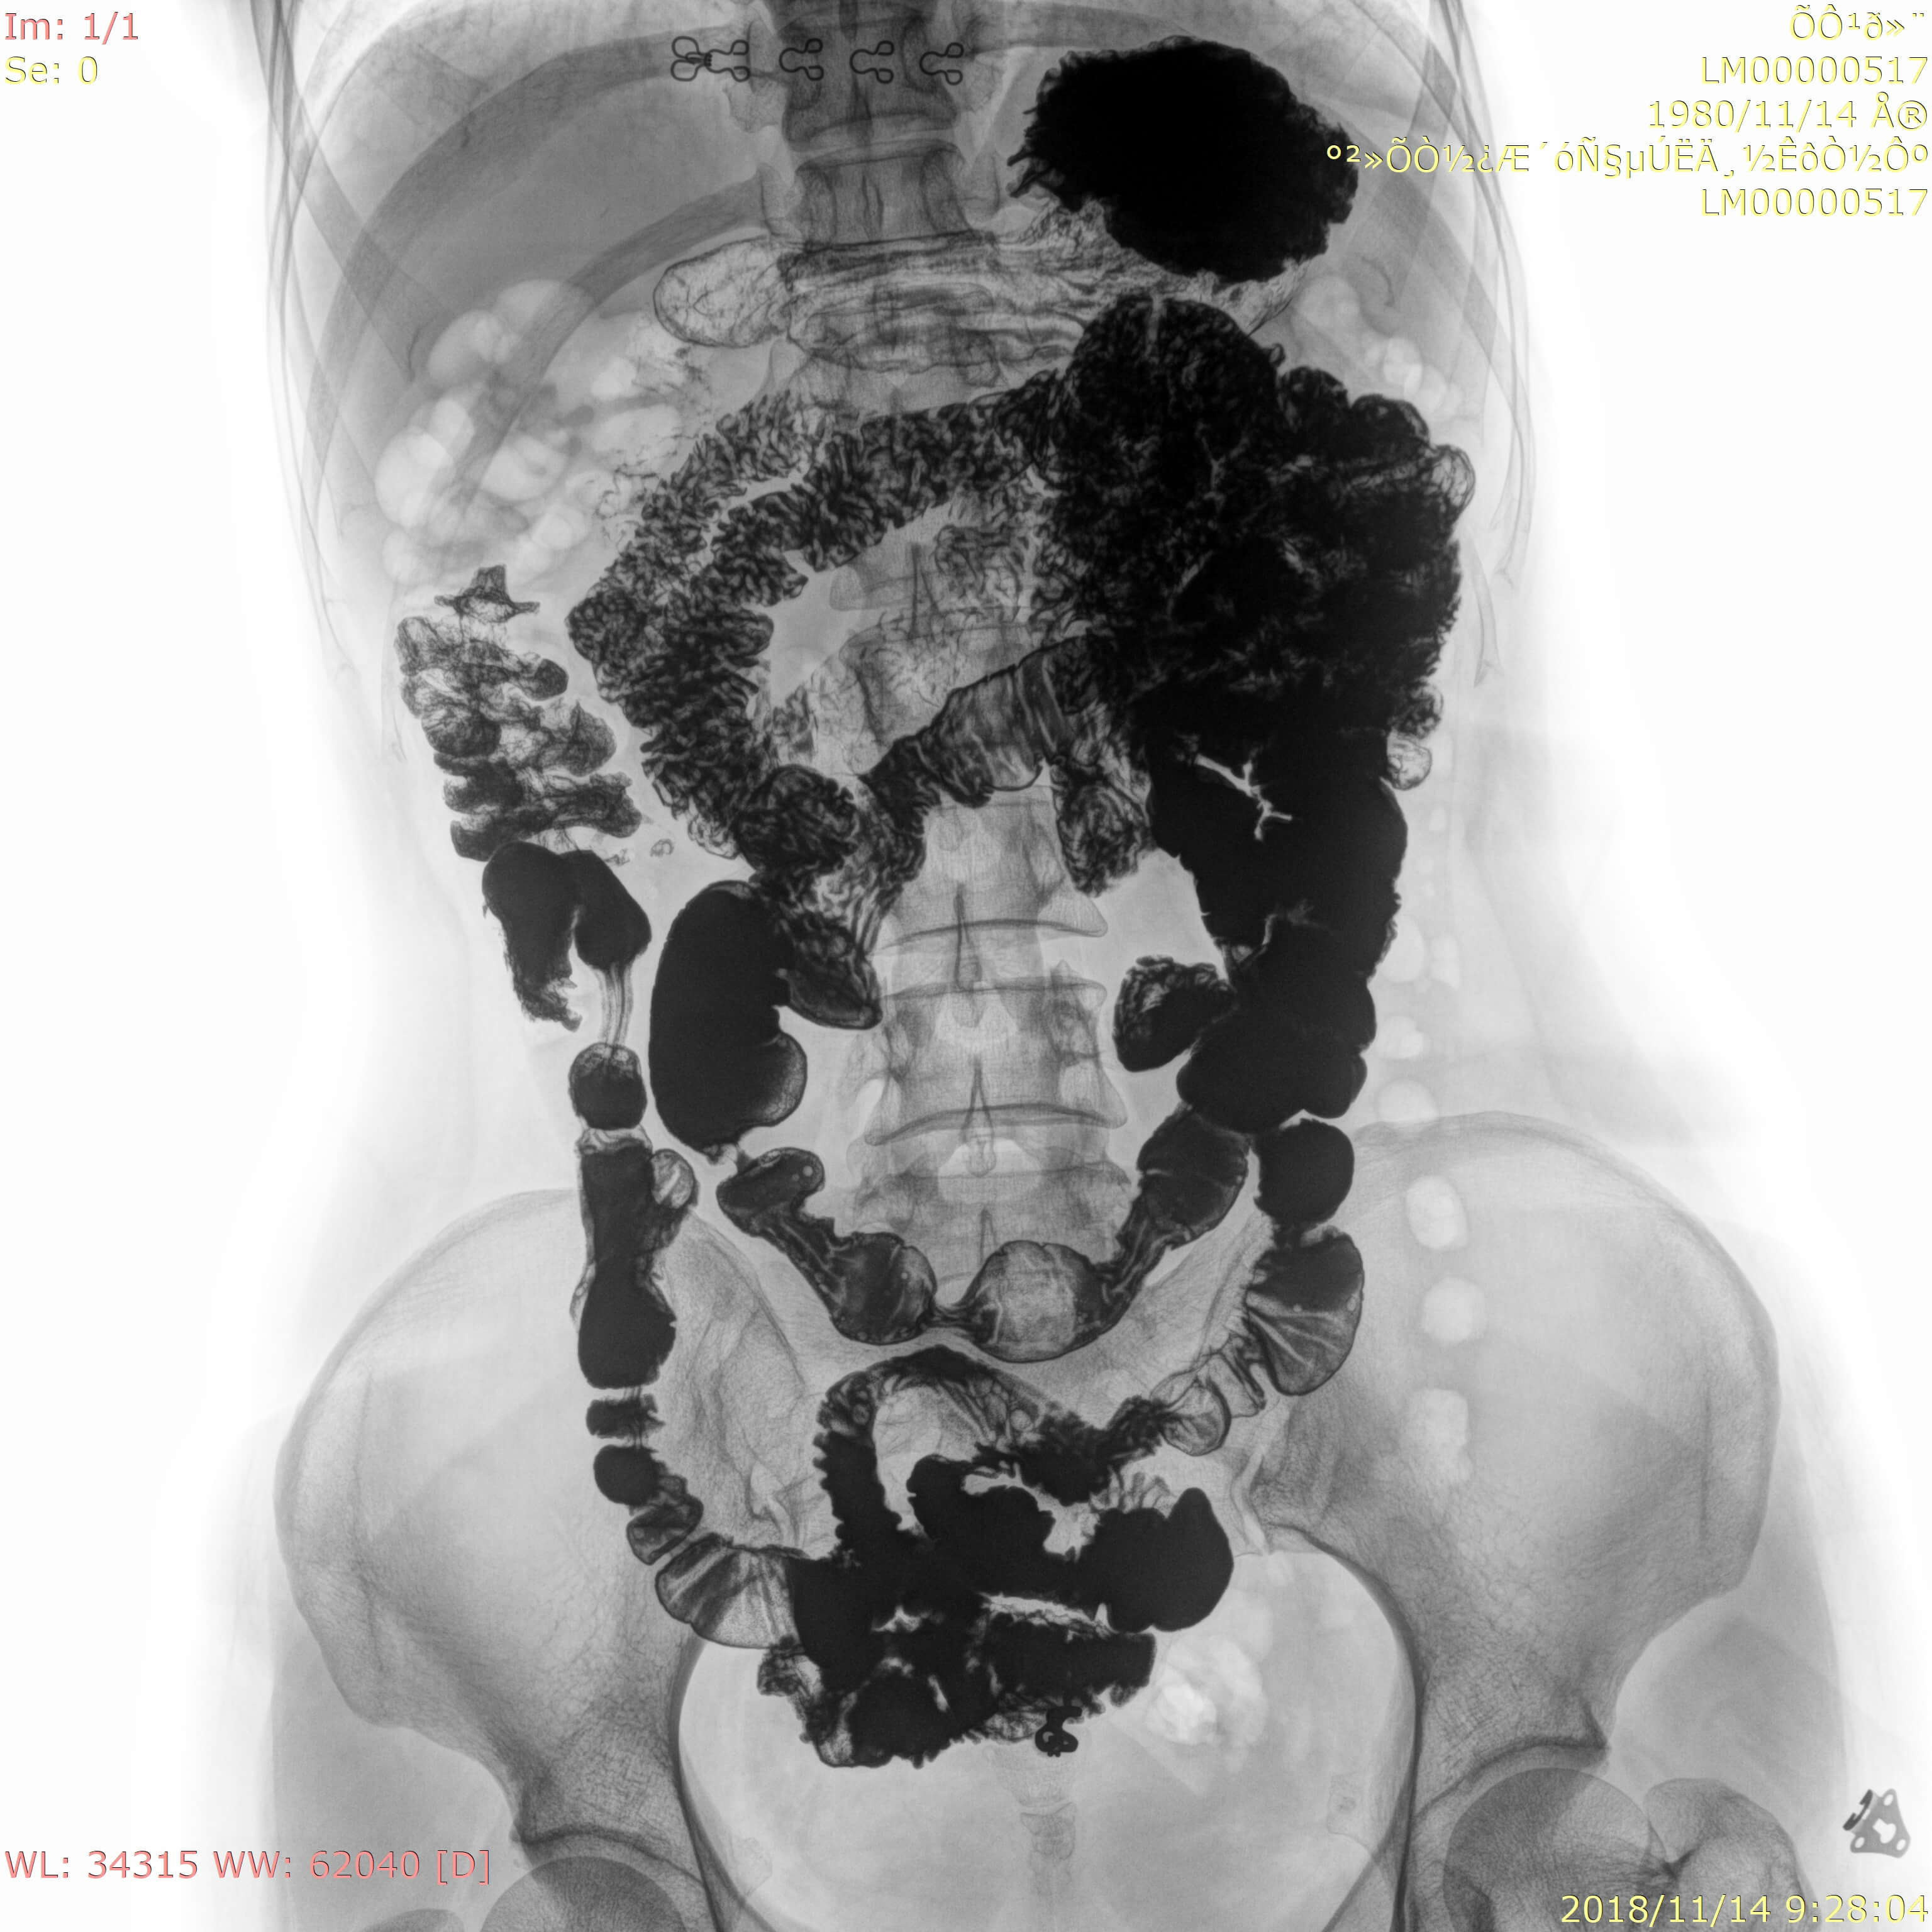

• Wide clinic applications